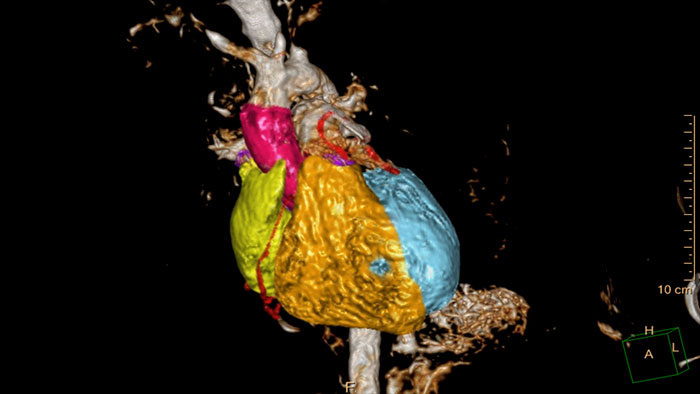

Detailed 3D visualization of the segmented heart

Allows 3D visualization of the heart and vessels anatomy on T1 3D or MRA acquisition. Manual editing tools as well as semi-automatic tools based on seed- and mask-based segmentation can be used as well as full automatic model-based heart segmentation.

Streamlined modeling workflow

Allows to view volumetric images of anatomical structures, perform segmentation, edit and combine segmented elements (tissues) into a 3D model.